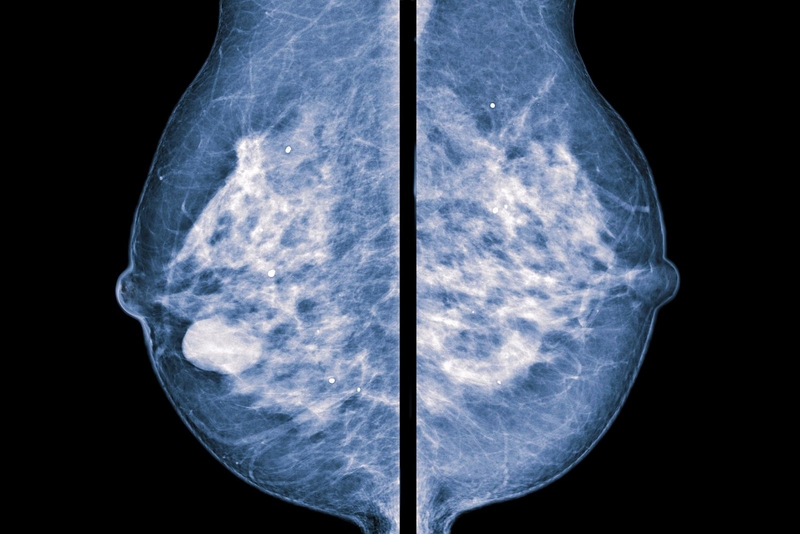

Hình ảnh u diệp thể tuyến vú

Nhũ ảnh: Khi chụp nhũ ảnh, khối u diệp thể cho thấy độ đậm cao, bờ đều, đa cung cà không có hiện tượng bị vôi hóa. Tuy nhiên nhũ ảnh không xác định được u diệp thể tuyến vú là u lành hay u ác.